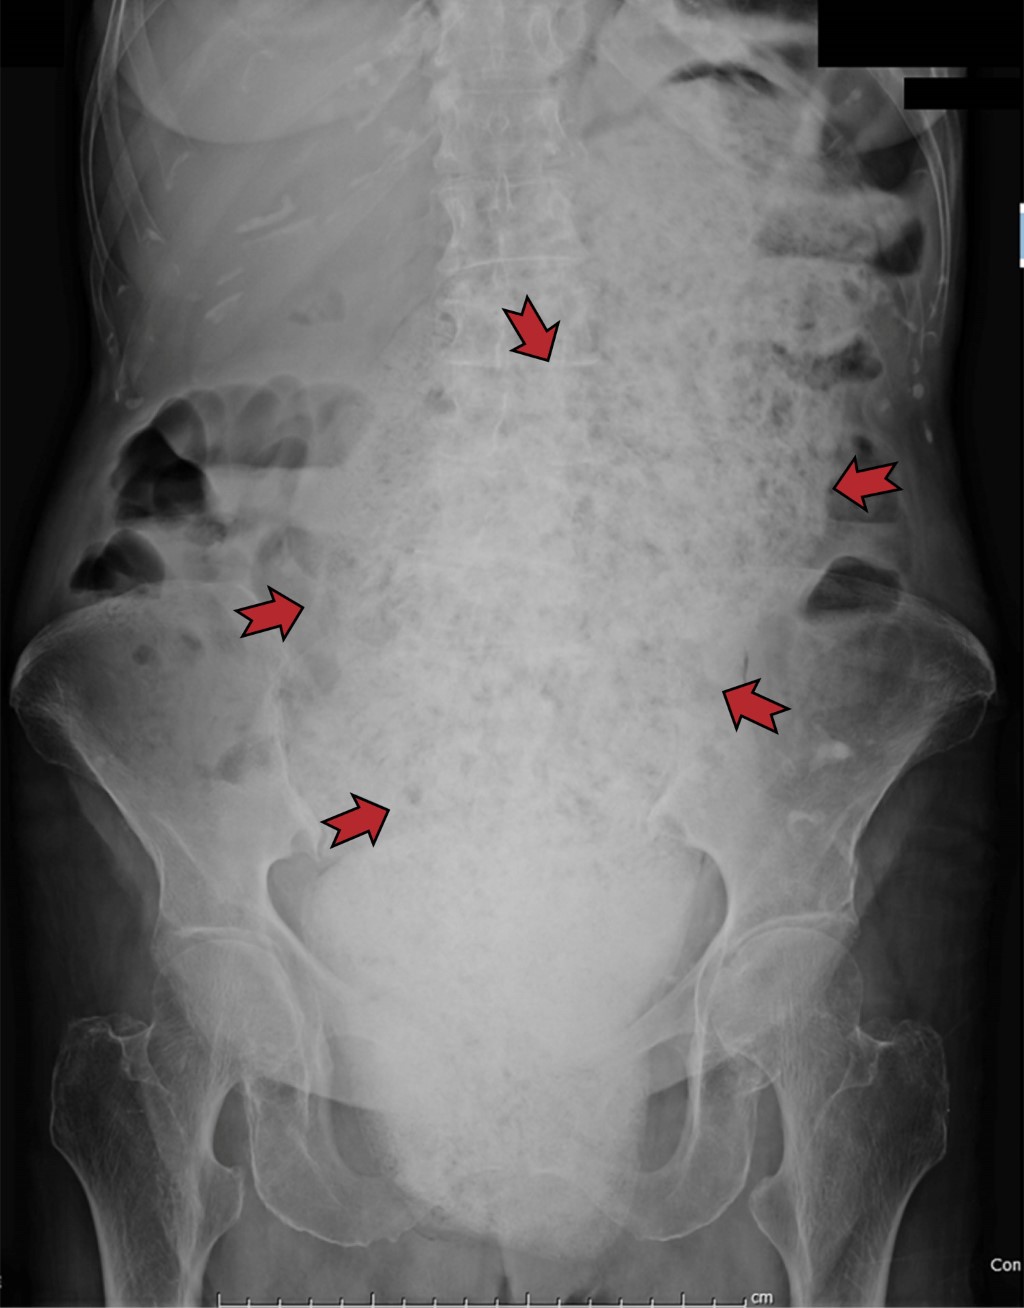

En el estudio radiológico simple, el hallazgo cardinal del AIA es la colección extraluminal extraintestinal de gas, pudiendo tener una o dos apariencias: 1) una colección aérea única que asemeja un asa intestinal, observándose como una colección de burbujas aéreas de localización difícil de diferenciar del contenido intraabdominal intraluminal intestinal y 2) un patrón moteado, mezcla de gas y de líquido que asemeja al contenido gástrico y/o colónico.1,4

El signo del migajón representa la suma de pequeñas cantidades de gas –radiolúcidas– atrapadas, entremezcladas con imágenes de radiodensidad de partes blandas, con efecto ocupativo y expansivo. Representa un hallazgo altamente sospechoso de la formación de absceso y/o colección intraabdominal. Su identificación condiciona una estrecha evaluación clínica exhaustiva, que, en concordancia con el estado clínico del paciente, favorece el establecimiento del diagnóstico clínico preciso. El signo del migajón tiene su diagnóstico diferencial (Figura 1), condicionado por la sobredistensión gástrica por material alimenticio. El bezoar consiste en el acúmulo de diferentes sustancias indigeribles en el tubo digestivo –intestinal o estomacal–, capaces de formar masas de volumen variable.

Aun con la identificación positiva de los hallazgos radiológicos en proyecciones abdominopélvicas simples, es indispensable realizar una evaluación más exhaustiva, determinando no solo que efectivamente hay un AIA, sino precisando su extensión y relación con otras estructuras, apoyando al médico precavido en su plan terapéutico y abordaje quirúrgico para un drenaje adecuado en pacientes críticamente enfermos.1,4